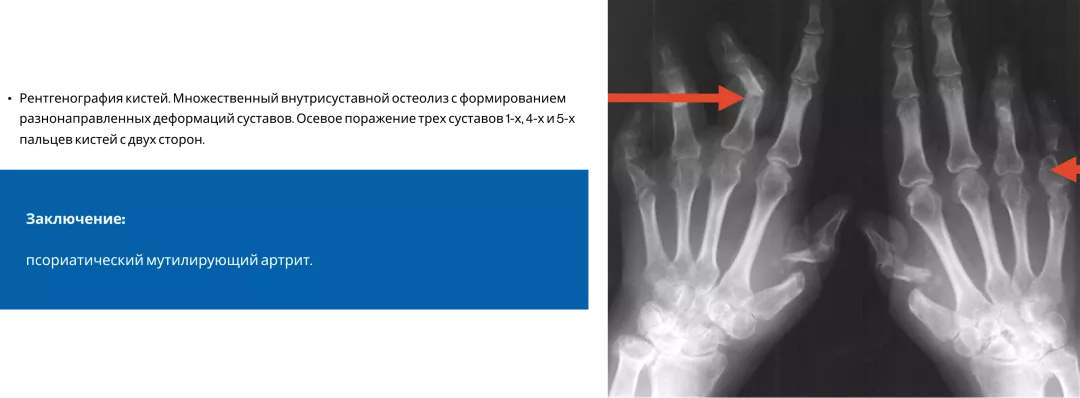

Псориатический артрит3

Псориатический артрит — заболевание, при котором в процесс могут вовлекаться как мелкие, так и крупные суставы, а также позвоночник. Структурные повреждения при ПсА являются основной причиной инвалидизации больных. Вот, к примеру, такой пациент с мутилирующим артритом не сможет выполнить элементарных движений — взять в руки ложку или мобильный телефон, застегнуть пуговицы или завязать шнурки. Все это, конечно, приносит большие страдания пациентам3,9.

Image

Frame 24061577 (1).png

Frame 24061578 (1).png

Типичные рентгенологические проявления ПсА — костные пролиферации и эрозии4

Frame 24062082 (2).png